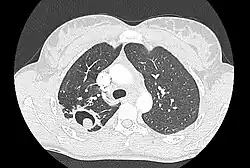

TAC en el que puede apreciarse la existencia de una caverna tuberculosa abajo izquierda, en cuyo interior se ha formado un aspergiloma masa redonda blanquecina. | ||